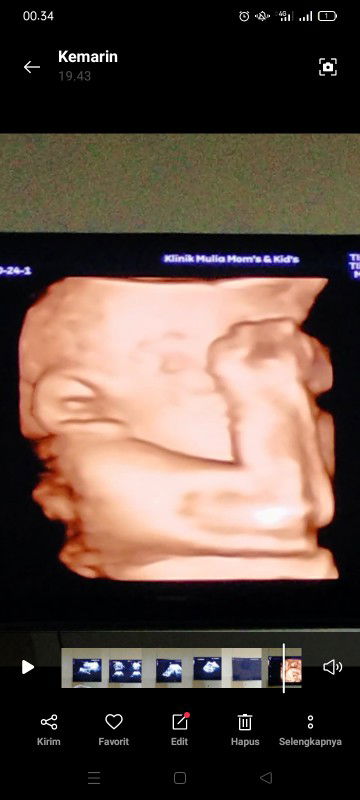

Hpl 12desember,usia kehamilan 29week tapi perut mash kecil apakah ada yang sama bun?🥰

sama bun, sya pas usg usia hamil 27 minggu bbj 1,200. skrg sya udh 29 minggu. janin nya aktif kdg kalo bergerak sakit rasanya perut . tpi sya senang bisa merasakan nya bun 😇

sama bun, hpl 12 desember. menikmati kaki &tangan yg sudah mulai bengkak. wktu periksa awal bulan kmren sudah naik 12kg 😂 alhamdulillah menikmati setiap perubahan...😊

Aku mah hpl Desember biasa aja sih bun, BB juga cuma naik 2kg, asal kata bubid sehat normal gak khawatir karena bbj tdk di tentukan dari besar dan kecilnya perut ibu nya

selagi dokter bilang gpp gak masalah si bun. ukuran perut bumil kan beda2, dan sesuai poster badan juga. yg penting ibu dan debay nya sehat2

sama bun aku hpl 9 desember skrg 30 week dan perut masih kecil, tpi gpp yang penting utun sama ibunya sehat dan pas lahiran lancar segalanya🤲

Ukuran perut ga pengaruh sama bbj bun, selagi hasil usg bbj normal sesuai usia ga usah dengerin kata orang. capek.. 🤗